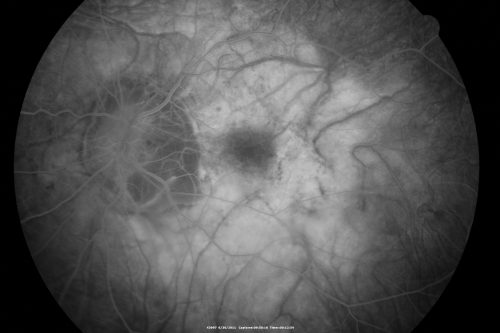

Myopic Traction Maculopathy - Vitreoretinal Traction - Possible Occult Neovascular Membrane

58-year-old woman was seen in the office on June 30, 2011. In 2002, her vision was 20/30.  Subsequent to that she had her left eye made her distance eye, which was dominate.  She had LASIK surgery on the right eye to make that her near eye and she was getting along well until about a year ago when she noticed substantial vision loss in the left eye only.  VISUAL ACUITY:  The near eye is 20/200, but she reads J2.   OS 20/100- and J16.